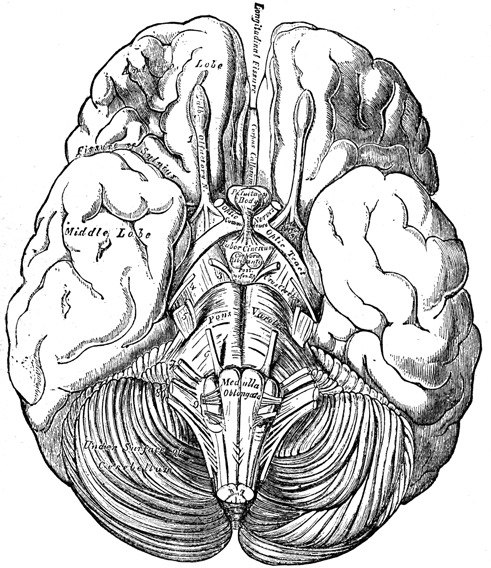

Chapter II—Structure of the Brain.

and the angular maps—View of the inferior surface of the

brain—Illustration and description of the parts—Interior view of

section on the median line—Divided and undivided surfaces-Corpus

of society—The lateral ventricles the centre of the

brain—Base of the ventricles, the great inferior ganglia of the

brain, corpora striata, and thalami—Their radiating fibres inclosing

a cavity—The thalami and their commissure and third ventricle—The

medulla oblongata, cerebellum, and arbor vitæ—The pons

Varolii and crura of the brain—the corpora quadrigemina, pineal

gland, fourth ventricle, and calamus scriptorius.